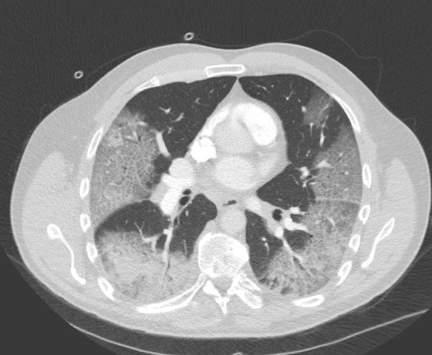

أحداث اليوم - نشر مدير عام مركز الحسين للسرطان الدكتور عاصم منصور، صورة عبر صفحته على فيسبوك، يظهر فيها رئتي مصاب بفيروس كورونا والتغيرات التي حدثت عليها.

وأوضح أن "كل ما هو أسود في هذه الصورة الطبقية للرئتين هو طبيعي ويمثل الجزء الذي يحتوي على الهواء منهما، أما ما هو أبيض فهو الجزء الذي احتله الفايروس وشرّد أهله (الهواء)".

وأضاف "بالتالي لم يعد صالحا لتبادل الأكسجين مع الدم وهو ما يؤدي الي ضيق النفس الذي يشعر به المريض ويستدعي مساعدته بضخ الهواء الى رئتيه صناعيًا".